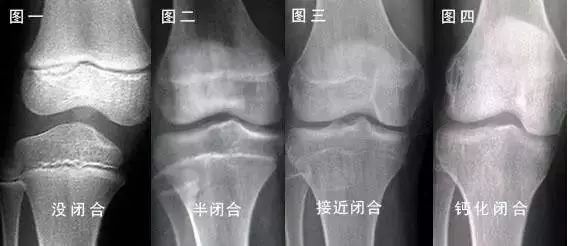

这条线就是骨骺线。人的身高,主要是长骨的增长体现的,长骨的最终长度决定了成年后的身高。

多数情况下,只要骨骺线未闭合,就还有长高的机会;反之,当骨骺线闭合时,长骨也就不再生长了,人的身高也就基本定型了。

在骨骺线彻底闭合之前,有两个长高黄金期:3岁以内和青春期。这两个时期,骨骺线处于开启状态,长骨有足够的生长空间。